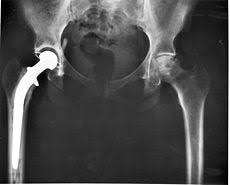

With the way his hip looked on imaging, the pain, crepitus, and difficulty in all WB positions, it is easy to see why a surgeon would want to perform a THA. His antalgic gait also displayed slight WS to the left, thus further causing a loss of SGIS to the right, perpetuating the far lateral derangement. Assuming his SGIS is equal at next visit, what would be your progression on ther ex?